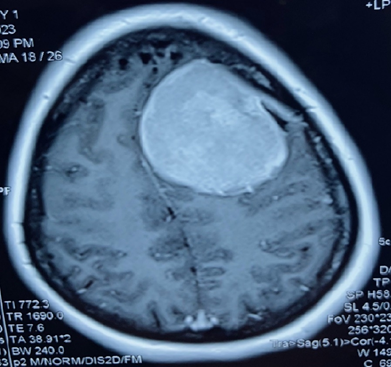

A-45-year-old right-handed lady with no significant past medical history presented with left sided hemicranial headache and a single secondary generalized convulsion. Clinical examination was normal with no other neurological deficit. Funduscopy revealed no papilledema. MRI brain without contrast identified a large left frontal extra-axial space occupying lesion with a dural tail suggestive of a meningioma with mass effect (Figure 1). Routine biochemical and haematological parameters were normal. Levetiracetam was started for seizure prophylaxis. Preoperative embolization of the tumor was planned followed by resection after 48 hours. Endovascular embolization was performed under conscious sedation. Vascular access was obtained via standard left femoral artery approach. Diagnostic angiography revealed tumoral blood supply from left middle meningeal artery and right ophthalmic artery (Figure 2). Super-selective microcatheterization of the left middle meningeal artery was achieved and tumorous feeders from ophthalmic artery were not embolized (Figure 3). Tumor embolization was achieved with polyvinyl alcohol particles (150 to 250 um). The patient was started on intravenous dexamethasone. Embolization of middle meningeal artery was followed by craniotomy after 48 hours. Simpson grade I resection of the tumor was achieved with around 300 ml periprocedural blood loss. There was no new onset neurological deficit following surgery. Post-operative hospital course was uneventful, and she was discharged home after 4 days. Histopathological examination revealed a WHO grade I meningioma. Review of medical literature was carried out to determine the optimal interval of resection following embolization of a large meningioma.

Figure 2 Pre embolization.

Figure 3 Post embolization.